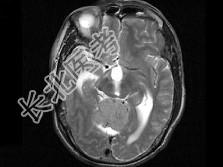

- 单项选择题男,61岁, 头晕头痛伴行走不稳1月余,根据所提供图像, 最可能的诊断是 ( )

A、胶质瘤

B、髓母细胞瘤

C、(天幕切迹缘)脑膜瘤

D、转移瘤

E、淋巴瘤